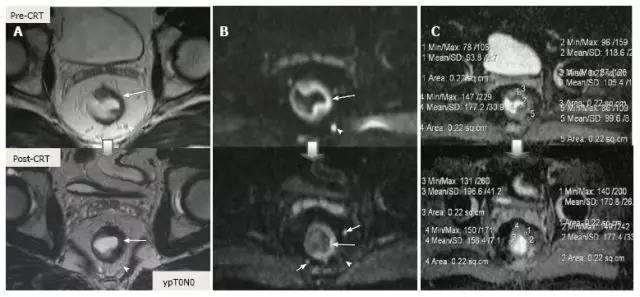

采用传统 MRI 序列对 CRT 后肿瘤重新分期的精确性差于初始分期,尤其在证实完全缓解(yT0),主要是很难将残留的肿瘤与纤维化、水肿和正常粘膜区分开,因此 CRT 后正常的 2 层直肠壁提示为完全缓解,而残留纤维化既可以是肿瘤残留也可以是完全缓解(图 17)。

实际上 CRT 后 T2 加权 MRI 后上纤维化的信号强度很低,而残留肿瘤区域则为中等强度,仔细评估高分辨图像和 DWI 是能区分小的残留病变和纤维化的(图 18)。

图 17. 新辅助放化疗后肿瘤重新分期。在不同患者的 T2 加权 MR 图像上分别显示(上:治疗前,下:治疗后)。A. 在 ypT0 直肠肿瘤中,治疗后的轴位图像显示正常的两层直肠壁(箭头),对应完全缓解;B. 在 ypT3 直肠肿瘤中,治疗后的轴位图像显示正常的双层直肠壁(箭头)。这是 MR 评估完全缓解的假阴性例子;C. 在 ypT0 直肠肿瘤中,原有肿瘤区域治疗后呈现厚的、纤维化的低信号强度疤痕(箭头)。